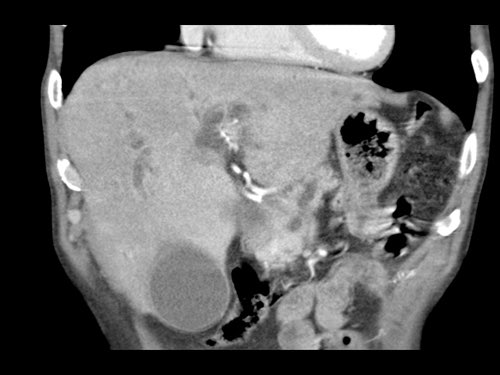

Tái tạo mặt phẳng coronal cho thấy một khối u lớn xuất phát từ cổ tụy với kiểu phát triển xâm lấn (hình A và B).

Có hiện tượng bao quanh động mạch thân tạng 360º (mũi tên trong A).

CT axial MIP tại mức động mạch thân tạng cho thấy hẹp động mạch gan chung bị bao quanh (mũi tên), rất nghi ngờ xâm lấn.